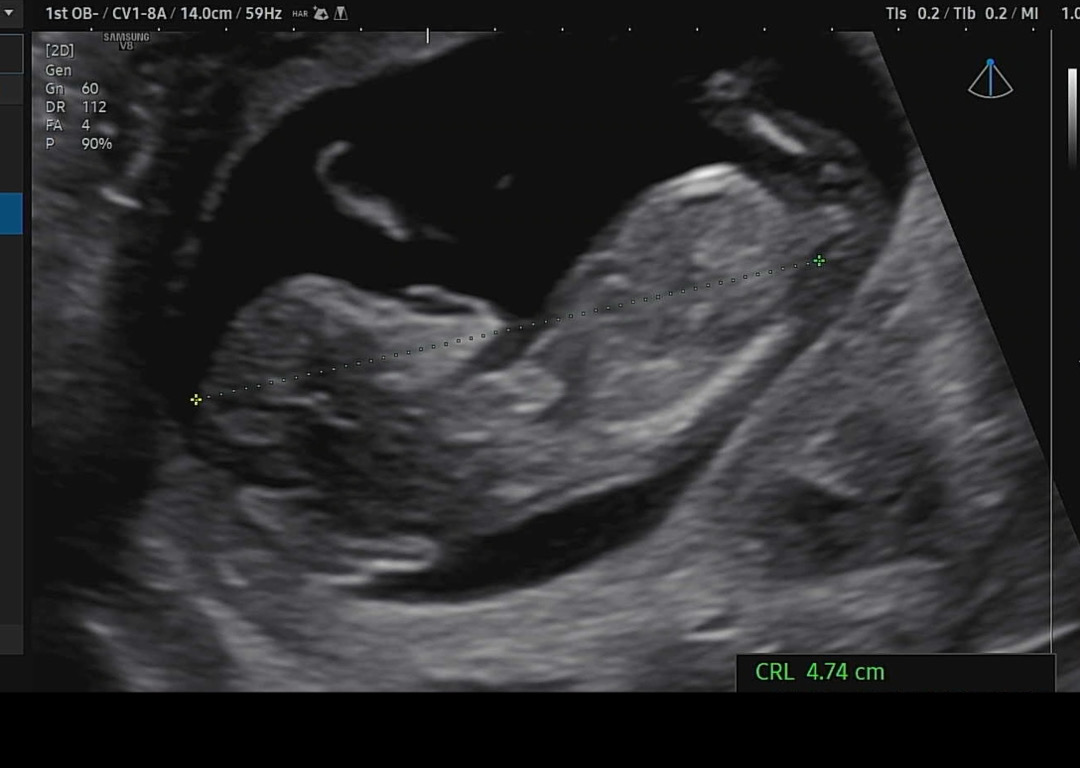

11주 5일에 갔는데 12주 크기더라구요 각도법 한번 봐주세요 !!! 😇